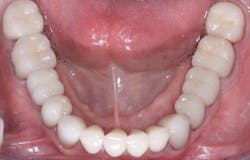

Luting characteristics on internal crown and external prep surfaces

The internal surfaces of current zirconia crowns are usually very smooth (figure 2). If the prep is adequate as described, this is usually not a problem. If there is any question about the potential zirconia crown retention, roughen the internal surfaces of the crown with a coarse diamond. If you do this, make sure you use a 3Y class 5 ceramic material. Many zirconia brands have modified material formulas that will not tolerate adjustment with a coarse diamond and will break. Similarly, roughen the external axial walls of the inadequate tooth preparation.